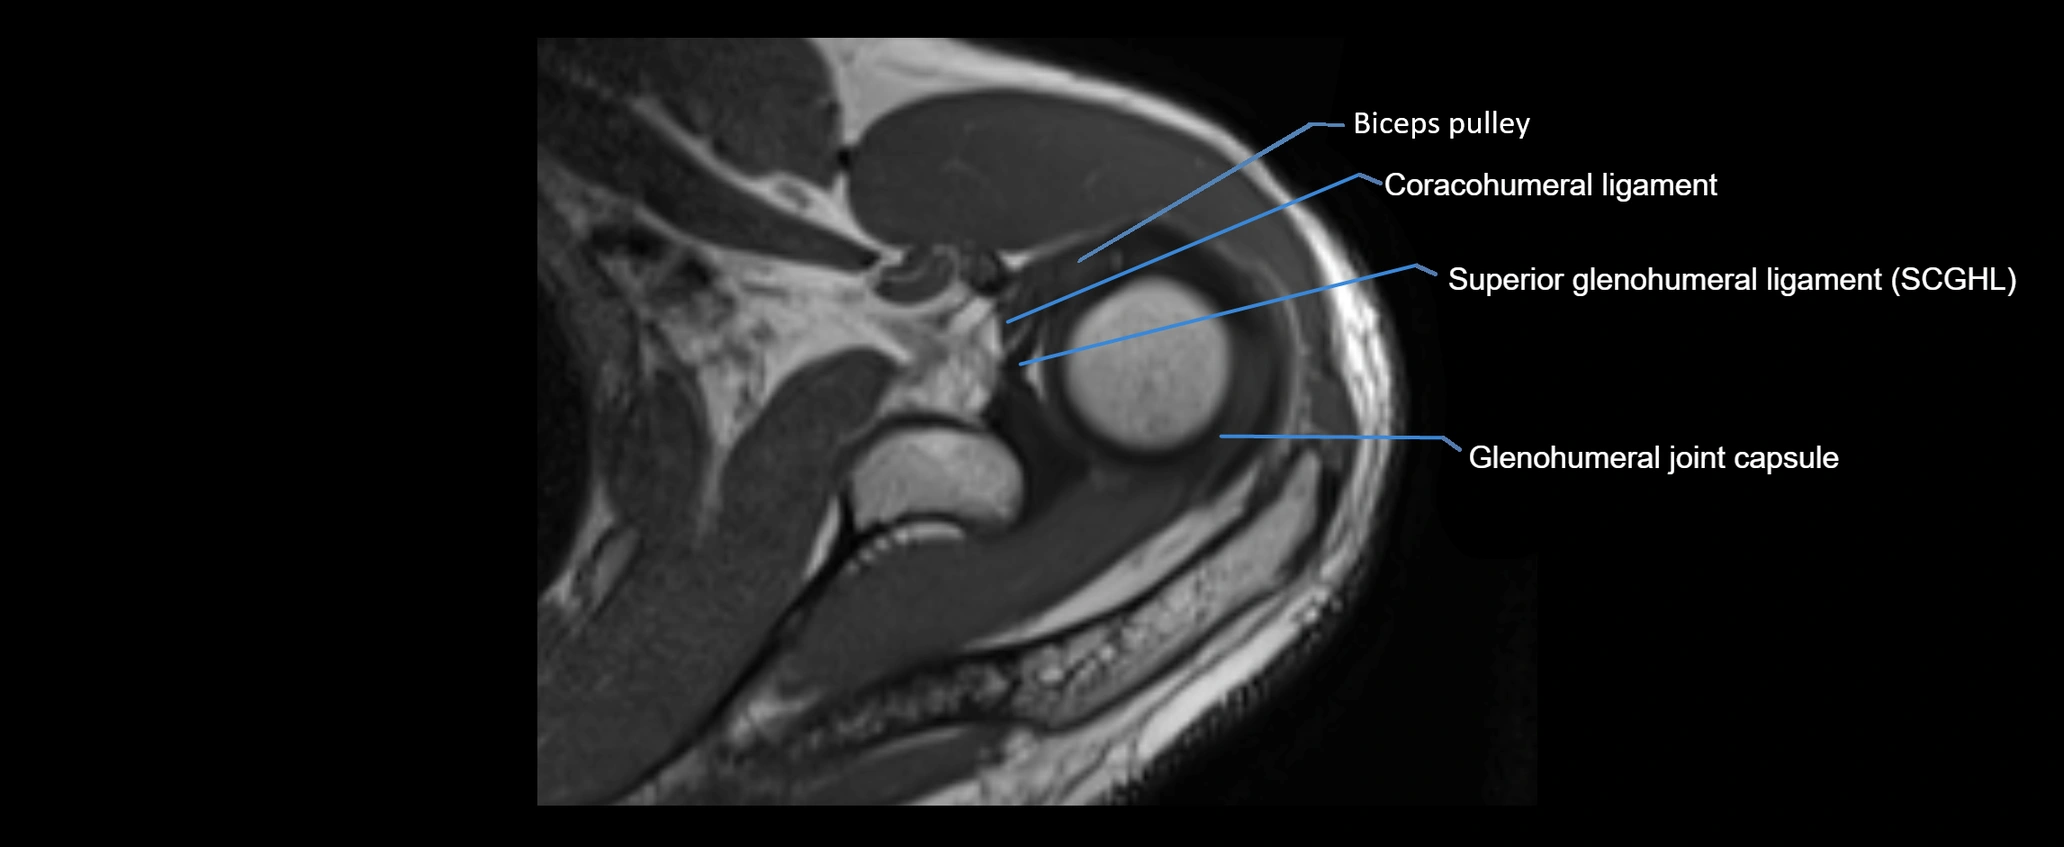

MRI images

image

MRI Appearance

• Proton Density Fat-Saturated (PD FS):

• Normal ligament: Low signal, uniform thickness.

• Partial tear or sprain: Bright signal or contour irregularity.

• Complete tear: Clear discontinuity with bright signal gap and joint effusion.

• Excellent for assessing joint capsule, coracoclavicular ligaments, and periarticular edema.